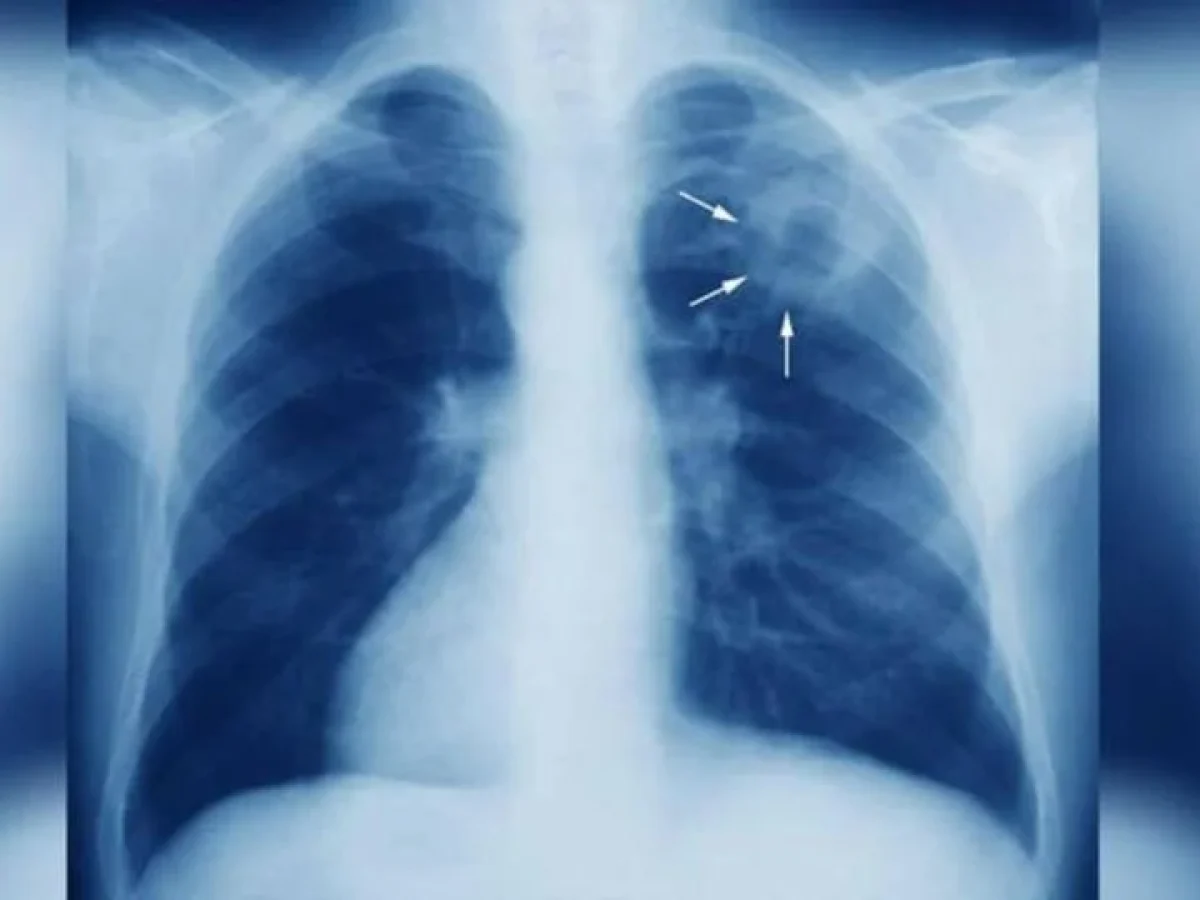

Πώς κολλάει και τι πρέπει να προσέχουμε

Η φυματίωση μεταδίδεται πολύ εύκολα με τα σταγονίδια του αέρα, συνήθως όταν κάποιος που νοσεί βήχει. Τα βασικά συμπτώματα που πρέπει να μας βάλουν σε υποψίες είναι:

- Επίμονος βήχας (ο οποίος πολλές φορές μπερδεύεται με απλό κρύωμα ή άλλες καταστάσεις)

- Πόνος στο στήθος

Αν η κατάσταση ξεφύγει, η λοίμωξη δεν μένει μόνο στους πνεύμονες, αλλά μπορεί να κάνει ζημιά και σε άλλα όργανα του σώματος.